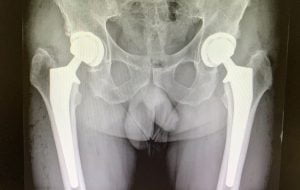

A artrose da anca frequentemente envolve as duas articulações causando dor intensa e mobilidade reduzida.

Quando isso interfere significativamente na sua capacidade de realizar as atividades quotidianas e o tratamento não cirúrgico já não for eficaz, o seu médico poderá recomendar uma prótese da anca bilateral.

A razão mais comum para uma da prótese da anca bilateral é uma artrose que causa dor e rigidez em ambas as ancas, interfere nas atividades da vida diária e reduz significativamente a qualidade de vida.

Para estes pacientes, com coxartrose bilateral incapacitante, este tratamento, Prótese Total da Anca Bilateral por Abordagem Anterior Direta, bilateral em simultâneo, é uma opção a privilegiar e a discutir com o paciente, não apresentado inconvenientes e riscos cirúrgicos acrescidos em pacientes selecionados e indicados, levando à resolução do problema, num só tempo, de uma forma mais simples e rápida, com custos diminuídos e ganhos pessoais e sócio-económicos.